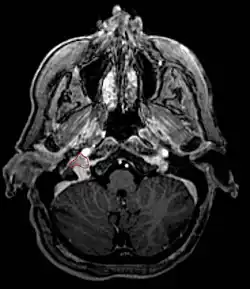

Paragangliome

Un paragangliome est une tumeur du système endocrinien. C'est la forme extra-surrenalienne du phéochromocytome. Les causes, l'expression clinique et le traitement du paragangliome sont identiques à ceux du phéochromocytome.

La tumeur est habituellement bénigne mais peut parfois être maligne, avec formation de métastases[1].